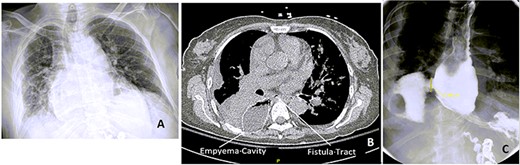

Three weeks postdischarge, she was re-admitted with fevers and shortness of breath and was found to be fluid overloaded. Esophagogram showed a large 2.5-cm defect in the mid-distal esophagus with extravasation of contrast material into right pleural cavity without communication to the bronchial tree (Fig. 1). An OGD further corroborated these findings. 16F Salem nasogastric tube was advanced into esophagus and placed into the bottom of the right pleural space.10F nasoduodenal feeding tube was also placed.

Chest x-ray (CXR), CT chest and esophagogram on the day of admission. (A) CXR showing right-sided pleural effusion and consolidation, (B) CT chest showing the empyema cavity and the fistula tract, (C) esophagogram showing a 2.5-cm mid-distal esophageal defect with contrast extravasting into the right pleural space.